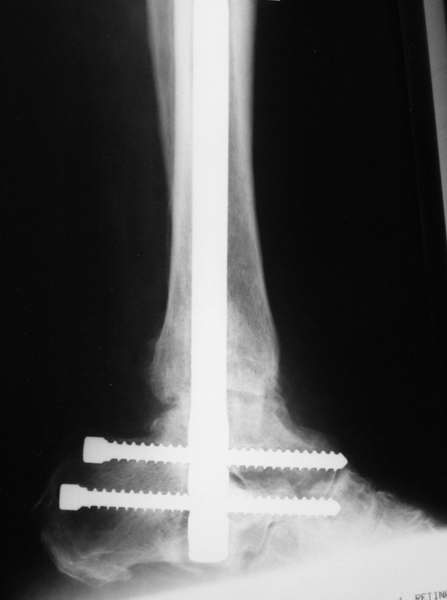

Да. Изначально планируется и подтаранный артродез.

Можно: 65-летняя пациентка, оперирована по поводу несросшегося в гипсе перелома лодыжек с патологической вальгусной установкой стопы и выраженным нарушением опрной функции. Оперирована через 6 месяцев после травмы. Рентгенограммы через 4 месяца после операции.

Само формирование и рассверливание канала для штифта и есть те "отдельные мероприятия", которых достаточно...